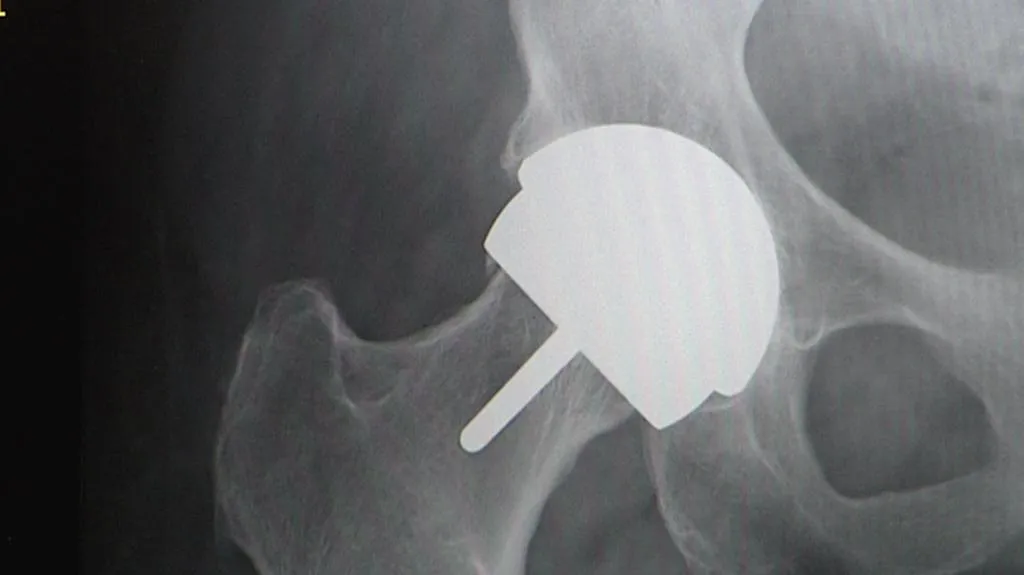

Sádry, čočky či očkování již patří mezi položky, za které si pacienti více než rok připlácí. A na seznamu nadstandardů se má brzy objevit další položka: kloubní náhrady. „V zásadě rozlišujeme dva základní typy endoprotéz. Cementovaná endoprotéza, která má hladký povrch a upevňuje se pomocí kostního cementu. A necementovaná protéza, kde se kanál ve stehenní kosti musí přesně vyfrézovat,“ uvedl Martin Krbec, primář ortopedie z FN Královské Vinohrady.

První kloubní náhrada se hodí pro starší pacienty s řídkými kostmi. Druhá lépe poslouží mladším a sportovně založeným lidem. Rozdíl je ale i v ceně. Klasická cementovaná náhrada je levnější. V současnosti rozhoduje o výběru protézy lékař.

„Cena cementovaných endoprotéz se pohybuje v průměru někde mezi patnácti a dvaceti tisíci. Necemetované endoprotézy jsou pochopitelně dražší, řekněme dvakrát až třikrát,“ řekl Krbec.

Dnes hradí zdravotní pojišťovny všechny typy endoprotéz bez ohledu na cenu. Už za rok by si ale pacienti měli za dražší kloubní náhrady připlácet. Třeba až zmíněných 40 tisíc korun, pokud tedy nebudou dražší kloub nutně potřebovat. Základní kloub zůstane zdarma stále.